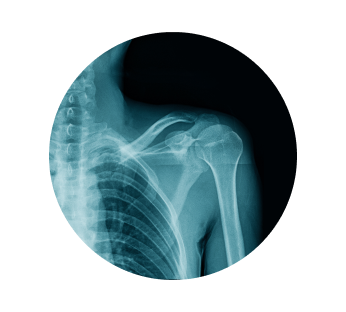

Рентген лопатки в Краснодаре